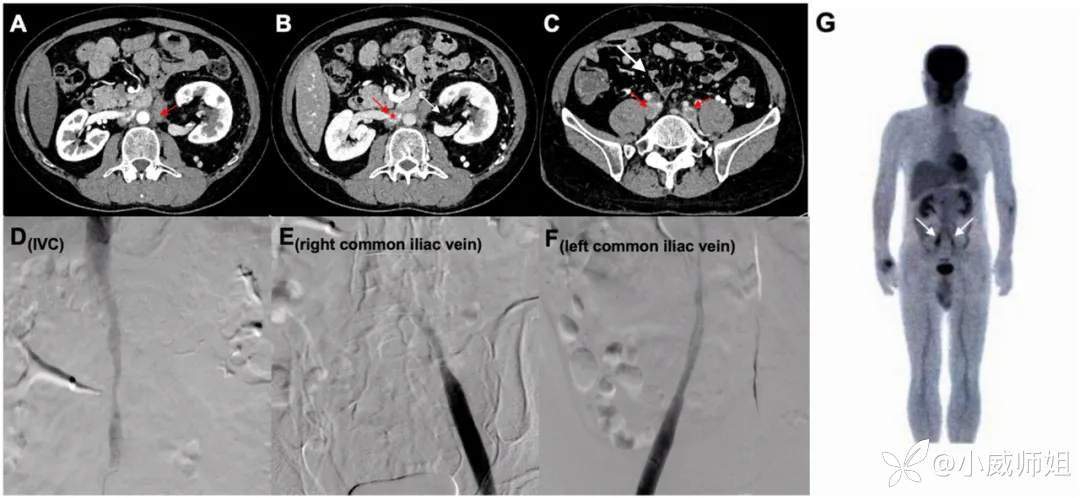

Wanki Ho, Weihao Li, Wenchang Nie, Yunshan Zhou, Chun Li, Yuzhou Gan, Hua Ye

本文报道一例特发性腹膜后纤维化,继发多支静脉难治性血栓形成,随后诊断为抗磷脂抗体综合征。对于继发于特发性腹膜后纤维化的静脉血栓形成病例,重要的是要筛查所有可能的血栓形成倾向的原因。

How to cite: Ho W, Li W, Nie W, et al. Antiphospholipid syndrome followed idiopathic retroperitoneal fibrosis in the same patient: a case report and review of literature. Rheumatol Autoimmun 2024; 4: 254-258. doi: 10.1002/rai2.12149